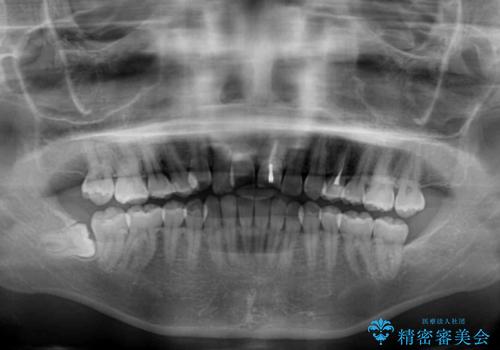

- 前歯のクロスバイトと神経を取り除いた後に変色してしまった前歯を気にして来院された患者様です。

ワイヤー矯正により矯正治療を行った後に、前歯の補綴治療を行うこととしました。

変色してしまった前歯は、反対側の歯と比べて歯肉が覆い被さっていたため、骨整形を含めた歯周外科処置を行い、歯肉ラインを整えることとしました。